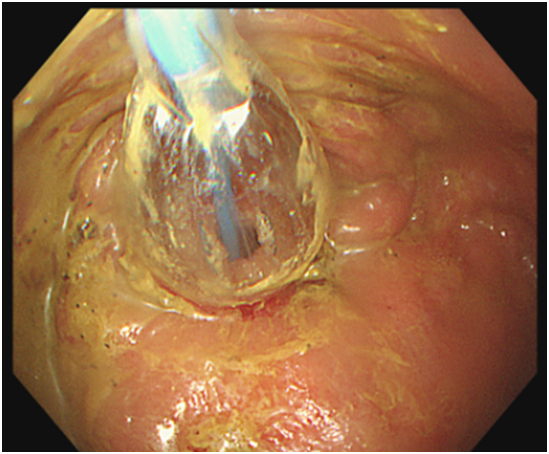

宁津县人民医院内镜中心开展首例内镜下肠道狭窄球囊扩张术